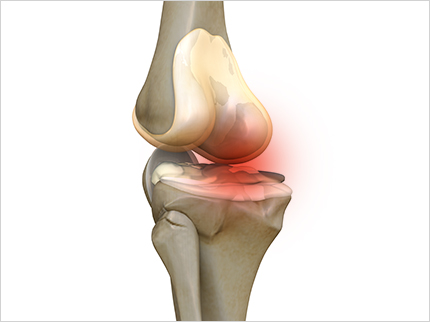

콘드로이친 효능 1. 연골 마모 예방

콘드로이친의 가장 큰 효능은 바로 연골 감소 예방입니다. 콘드로이친은 연골에 영양분을 공급하는 역할을 합니다. 연골에 충분한 영양분들 공급하여 연골의 탄력과 힘을 보충하여 연골이 마모되는 것을 예방해 줍니다. 한 실험울 통해서 콘드로이친을 일정하게 섭취한 사람과 아닌 사람의 연골 마모 속도가 2배 이상 차이가 난다는 결과가 있습니다.

콘드로이친 효능 6.연골의 재생

콘드로이친은 연골 손상을 막을 뿐만 아니라 손상된 연골 주성분인 연골세포를 재생시킴으로써 연골 기능을 향상시키는데 도움을 주어 연골의 통증으로 고통 받는 분들에게는 보행 편의성을 증대시켜 삶의 질을 향상 시킬 수 있습니다.